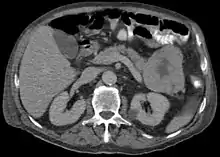

ACC are typically large, up to 10 cm, and soft compared to pancreatic adenocarcinoma, lacking its dense stroma. They can arise in any part of the pancreas.[2]

Light microscopy of an acinar cell carcinoma biopsy typically shows granular appearance.[6] Immunohistochemistry is usually positive for trypsin, chymotrypsin and lipase.[6] On genetic testing, altered genes/proteins are typically found for p53, SMAD4, APC, ARID1A and GNAS.[6]